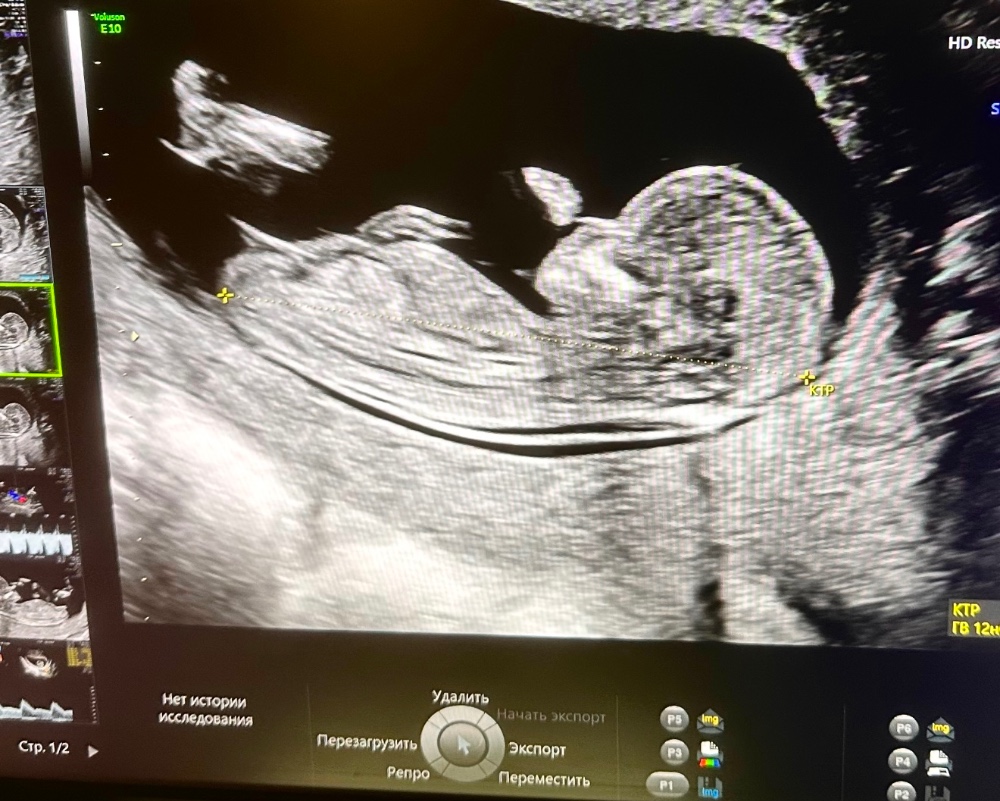

Тут видно только ножки. Полосой бугорок на этом сроке очень похож у девочки и мальчика. У мальчика он только-только начинает приподниматься. Вот мальчик срок 11.1

А это сейчас срок 11.3 был. Ходила вчера на скрининг, там ничего не показали(( но вроде пока что такой же ровный.

Марина, да, качество узи отличное! У меня плохое качество сейчас, все размазанное. И видно конечно, что это девочки. Сейчас даже форма тела у вашего малыша другая. Желаю вам мальчика❤️